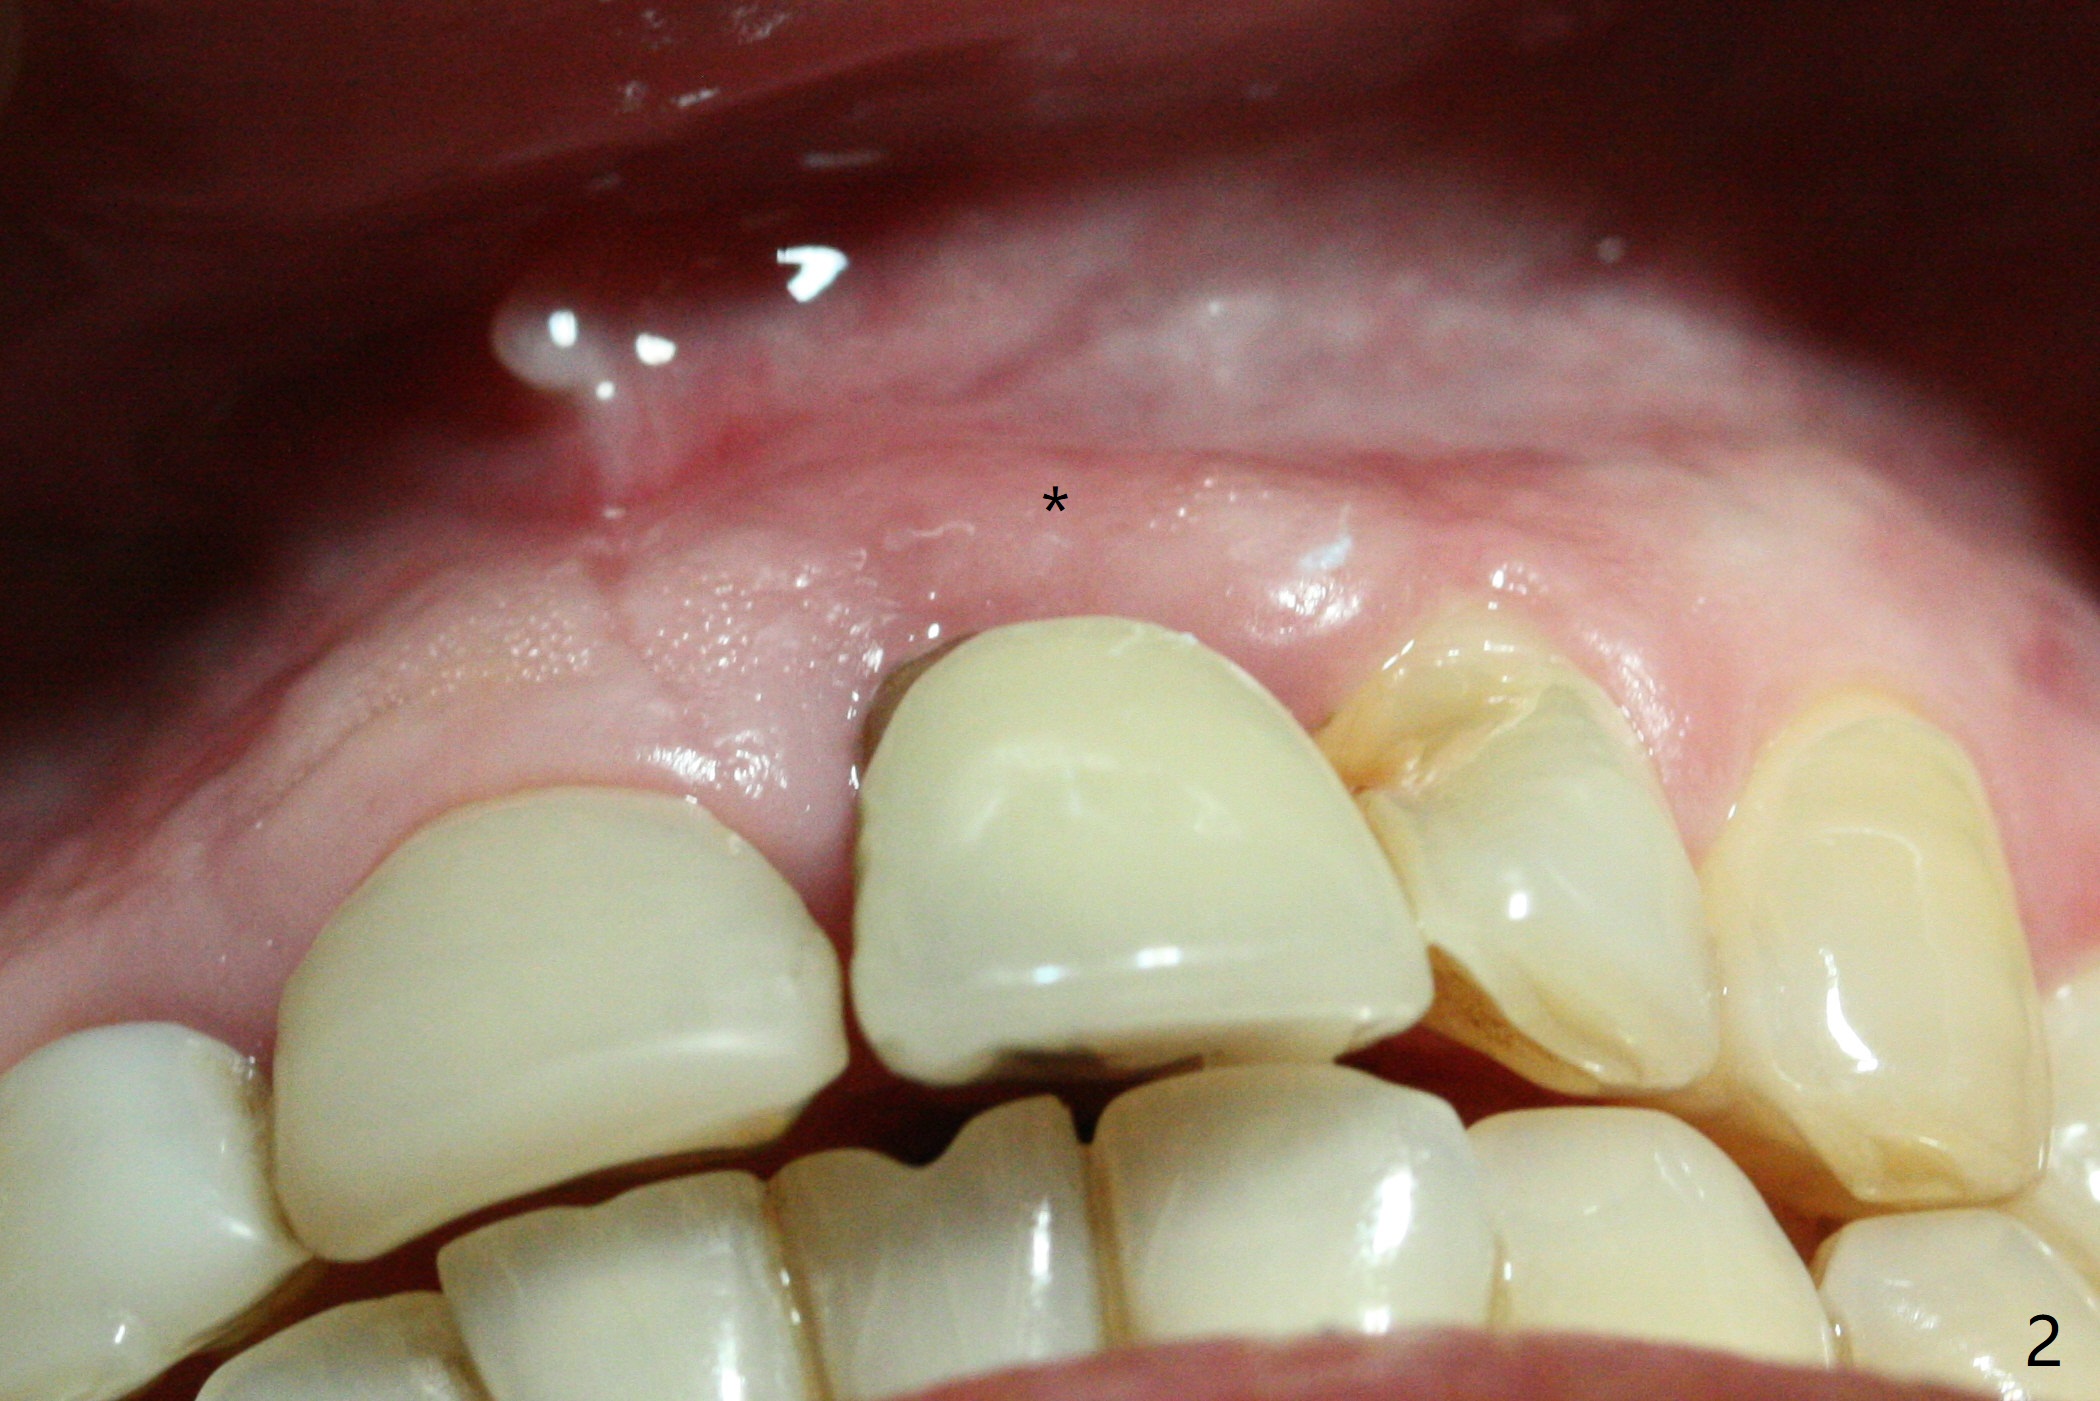

In spite of the incisobuccal shift of the tooth #9 with gingival recession (Fig.1) and loss of the buccal plate (intraop finding), there is no buccal contour collapse (Fig.2 *), due to the presence of the buccal bone of the neighboring teeth and the root of the affected tooth. After extraction, osteotomy (Fig.3) and dummy implant try in (Fig.4), a definitive implant is placed palatally with the buccal gap (Fig.5 *). In fact there is mild buccal contour collapse prior to bone graft (Fig.5 arrow). When allograft (Vera, Fig.6,7 *) is packed buccal to the implant and overlying abutment as a solid support, the buccal contour seemingly returns normal (Fig.6 arrowhead). An immediate provisional is fabricated to prevent loss of the bone graft during healing period. Bone graft kept in place by the provisional turns yellow 6 days postop (Fig.8). The buccal plate remains strong, while the fistula becomes indistinguishable. After adjustment of the provisional margin a few times (nearly 3 months postop, Fig.9,10), the gingival margin appears to have grown incisally, as compared to Fig.1. There is minimal buccal bone collapse (Fig.10). Dislodgement of the abutment and provisional forces her to return 1 year 4 months postop; the socket has healed (Fig.11). The buccal plate is not concave 1 year 4 months postop (Fig.12). The gingiva is slightly recessive (Fig.13) with mild buccal plate concavity (Fig.14) immediately before cementation. The implant could be placed ~ 1 mm deeper (Fig.15).